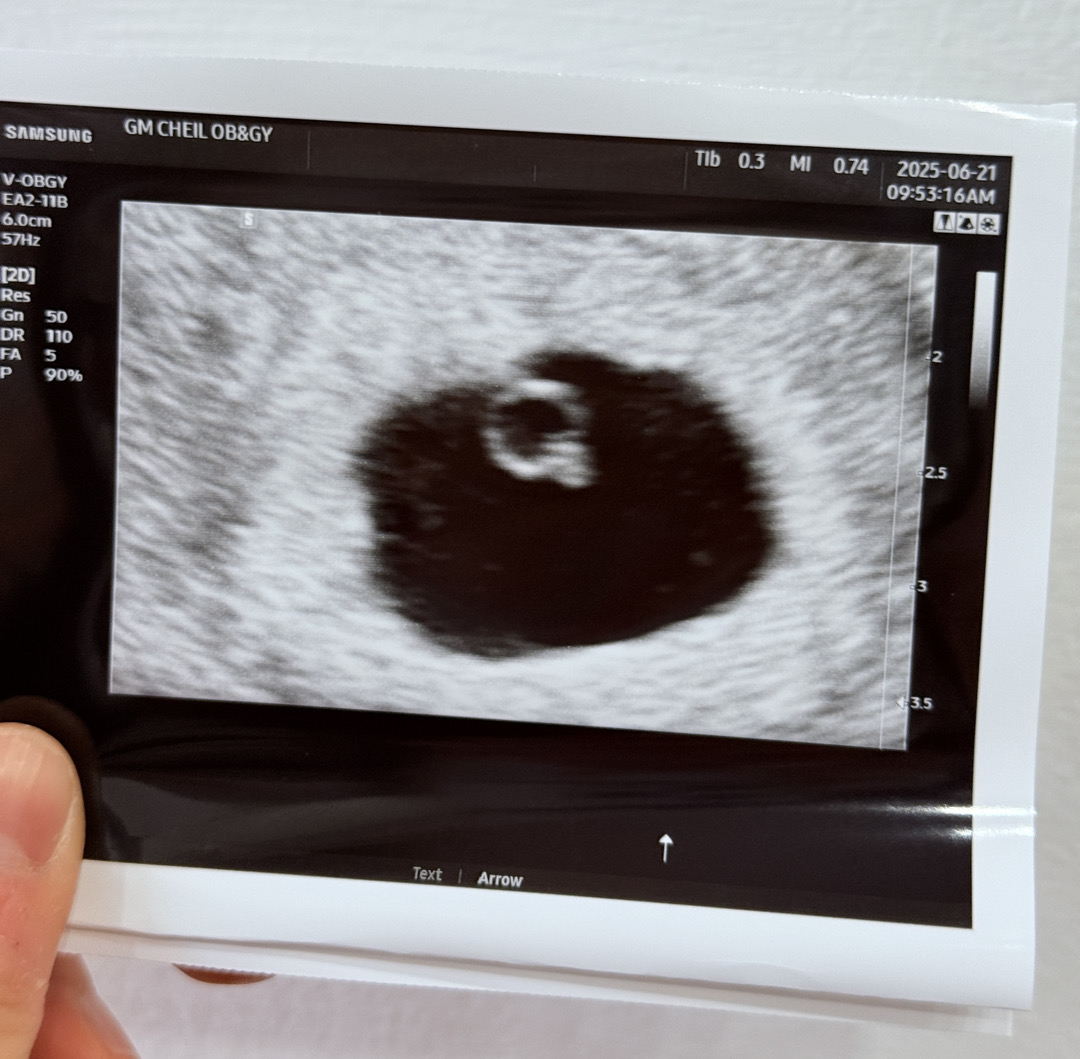

6주 심장소리 듣고왔어요!

5.10 막생 6.5 두줄 확인 6.13 아기집 확인(4w 6d) 6.16 난황 확인(5w 2d) 6.21 심소🖤(6w 0d) 매번 초음파볼때마다 달라져있어서 신기하고 감사하네요ㅠㅠㅠ🤍 다이아반지를 봐버리다니..! 모든 산모분들 화이팅입니다!!!

아기 크기는 3mm 입니다 :)